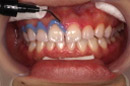

| 染め出しを行います (これは、染め出された歯についたタンパク質膜を、見やすくしてしっかりと落とすためです。) |